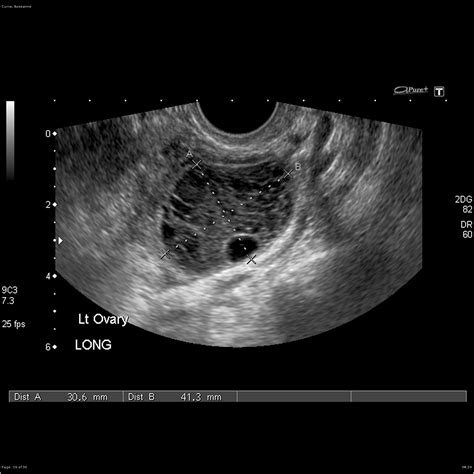

When a physician suspects a dermoid cyst ovary, they will utilize specific diagnostic tools to confirm the presence, size, and location of the mass. Imaging is the gold standard for diagnosis because the specific contents of these cysts—such as fat, calcium (teeth/bone), and fluid—have distinct appearances on scans.

Pelvic Ultrasound The primary tool to visualize the cyst and determine if it is solid or fluid-filled.